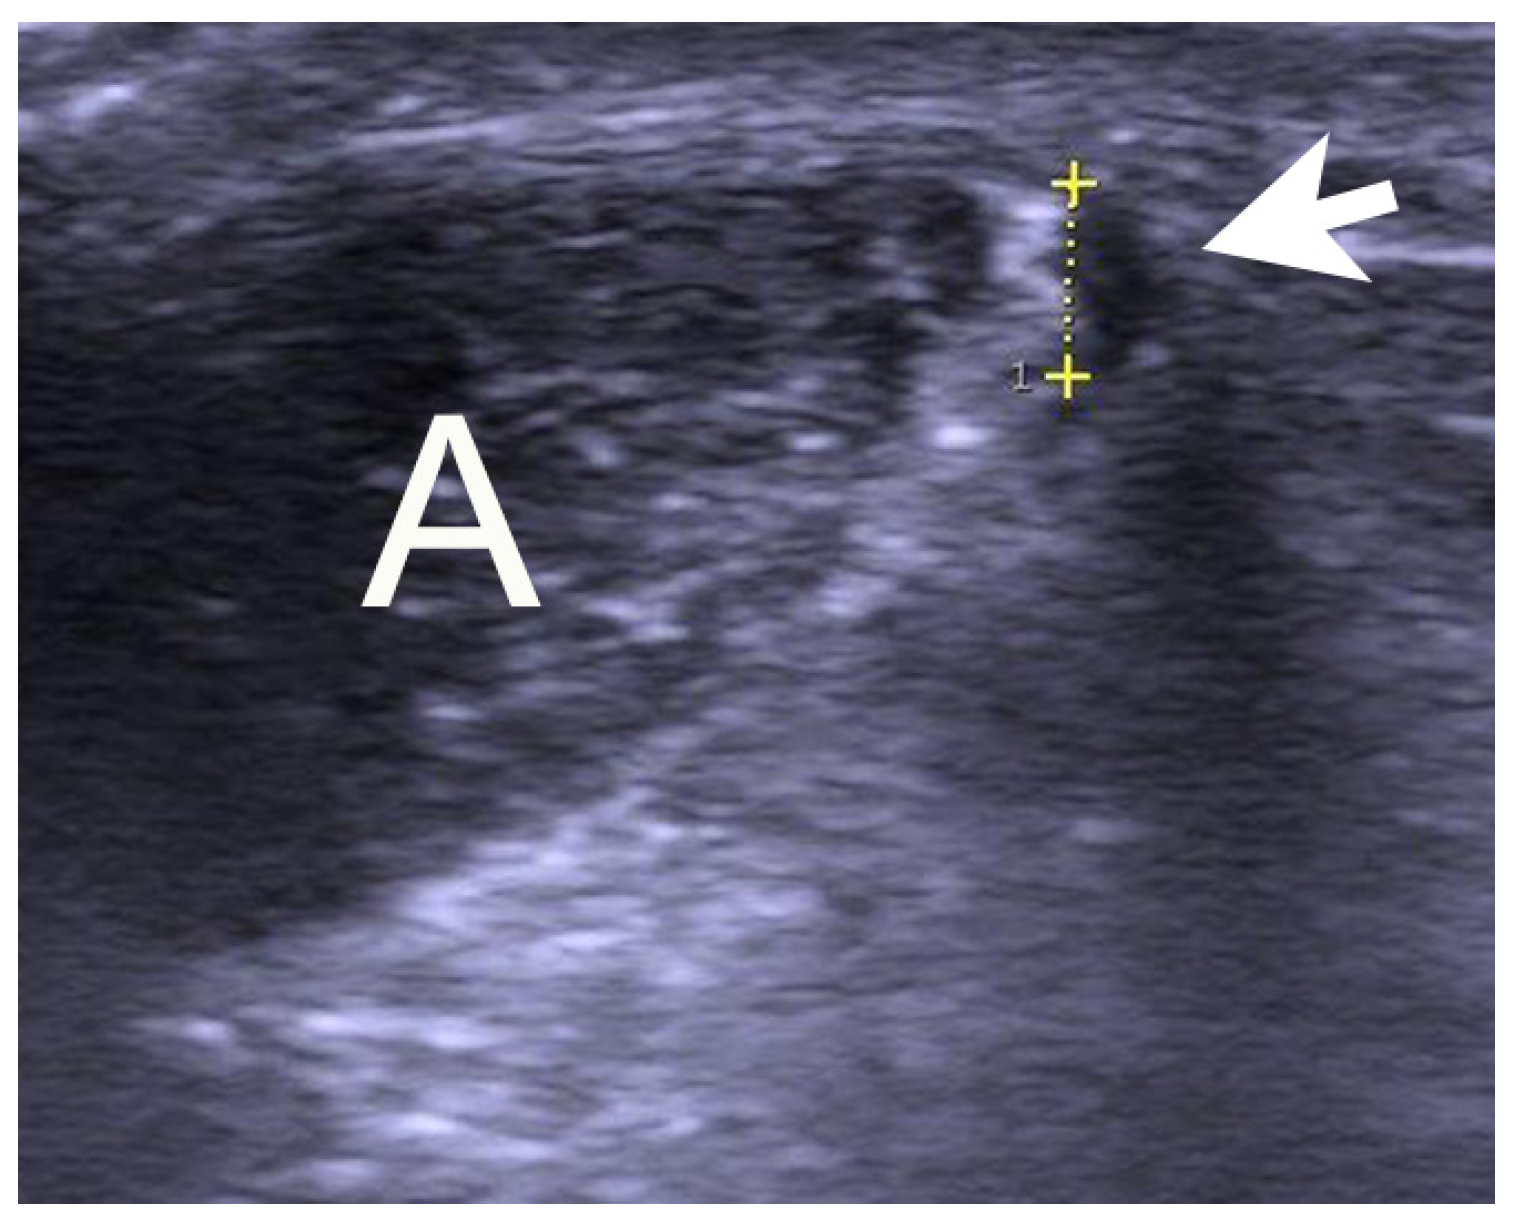

A longitudinal skin incision (1–2 cm) was placed on the medial side of the Achilles midportion. Following blunt dissection, the plantaris tendon was carefully identified (Figure 2), released, and followed distally and proximally from the skin incision. The plantaris was cut in both ends, resulting in 5–8 cm of the tendon being extirpated. Any vascularized fat tissue inter-positioned between the Achilles and the plantaris tendons was scraped. Then, the traditional Achilles scraping procedure was performed [23,24,28]. In the regions with US + CD-verified high blood flow outside the ventral and medial side of the tendon, the tendon was completely released from the ventral soft tissue. This scraping procedure was performed by sharp dissection using a scalpel, staying close to the ventral tendon. Following careful hemostasis using bi-polar diatermia, the skin was closed by single non-resorbable sutures, which were removed after 3 weeks.

Figure 2. Surgery of a patient with midportion Achilles and plantaris tendinopathy. There is a thick and wide plantaris tendon located close to the medial side of a thickened Achilles midportion.